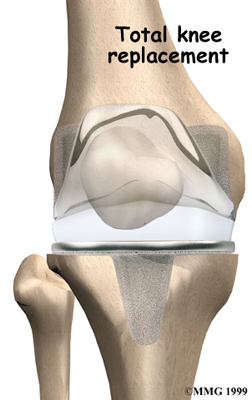

Artificial Knee Replacement

An artificial knee replacement is the ultimate solution for advanced knee OA.

Surgeons prefer not to put a new knee joint in patients younger than 60. This is because younger patients are generally more active and might put too much stress on the joint, causing it to loosen or even crack. A revision surgery to replace a damaged prosthesis is harder to do, has more possible complications, and is usually less successful than a first-time joint replacement surgery.

Related Document: FYZICAL East Naples Guide to Artificial Joint Replacement of the Knee